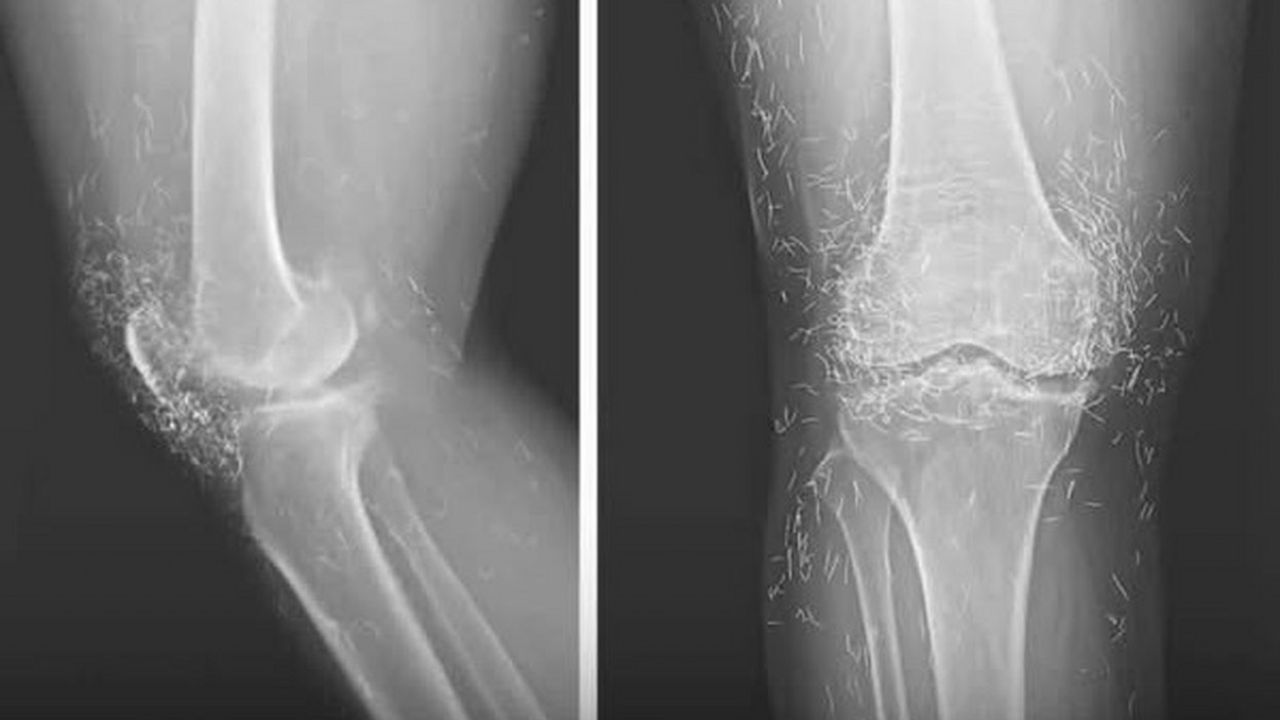

65 yaşındaki kronik osteoartrit hastası bir kadının diz ağrısı şikayetiyle hastaneye başvurmasının ardından çekilen röntgen, doktorları adeta şaşkına çevirdi. Görüntülerde, kadının diz eklemlerine dağılmış şekilde yüzlerce küçük altın iplik saptandı. Bu durumun, geçmişte uygulanan "altın iplik akupunkturu" adı verilen geleneksel bir tedavi yönteminden kaynaklandığı ortaya çıktı.

Bu vakada, altın tellerin çıkarılmasının dokuya daha fazla zarar verebileceği düşünülerek müdahale edilmedi. Röntgende ise teller adeta bir takımyıldız gibi parlıyor, ancak hastanın ağrılarını dindirmekte ne kadar etkili oldukları ise tartışma konusu.